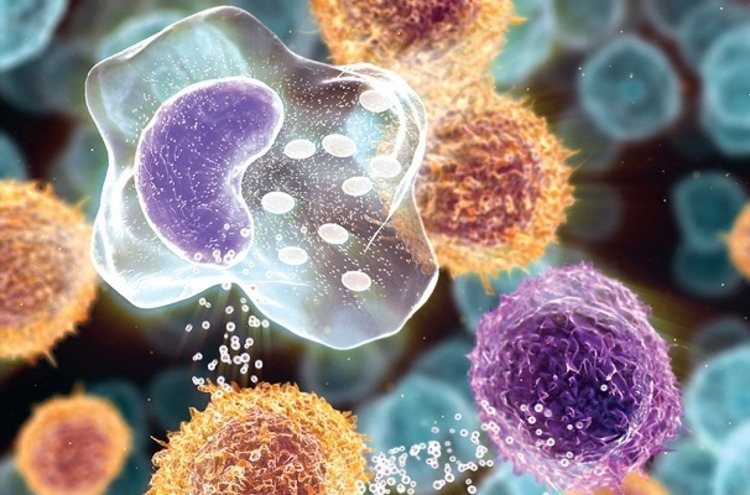

Austrálski vedci zistili, že zdravé črevné baktérie sa v maternici vyvíjajú už po piatich mesiacoch. Črevný mikrobióm je komplexný ekosystém mikroorganizmov, baktérií, vírusov, húb a ďalších foriem života. Toto prostredie je nevyhnutné pre prežitie a je spojené s trávením, zdravím mozgu a srdca, kontrolou hmotnosti a znížením hladiny cukru v krvi.

Procesy a plesne v čreve ovplyvňujú aj niekoľko autoimunitných chorôb. Patrí sem rakovina, roztrúsená skleróza a autizmus. Nový objav, vedený vedcami z La Trobe University, vrhá nové svetlo na vyvíjajúci sa imunitný systém plodu, črevá a mozog. Vedci pomocou extrémne prísnych kontrol skúmali vývoj mikrobiómov pozdĺž gastrointestinálneho traktu u teliat pred narodením. Inovatívna štúdia ukazuje, že mikrobióm sa líši v rôznych zložkách fetálneho gastrointestinálneho traktu. Je to prvá štúdia, ktorá úplne eliminuje potenciál mikrobiálnej kontaminácie a zastavuje dlhodobú teóriu, že k vývoju plodu dochádza v sterilnom lone. Ashley Franks, profesorka La Trobe University, uviedla, že výskum prevracia túto oblasť vedy naruby.

Od detstva do dospelosti sú bilióny mikrobiálnych buniek základnou súčasťou biologických a fyziologických funkcií. To tiež zachováva celistvosť črevnej sliznice a dokonca chráni pred chorobami. Vedci doteraz predpokladali, že prvý črevný mikrobióm dieťaťa pochádzal z prostredia, do ktorého sa narodilo. Tieto výsledky nepochybne potvrdzujú, že zdravé črevné baktérie sa usadzujú v čreve pred narodením a menia budúcnosť výskumu plodu a chápania toho, ako mikrobióm ovplyvňuje vyvíjajúci sa imunitný systém. Vedci identifikovali 559 bakteriálnych a 1736 diskrétnych archeobaktérií sekvenovaním ďalšej generácie piatich zložiek fetálneho gastrointestinálneho traktu a plodovej vody.

Štúdia ukázala, že distribúcia týchto mikroorganizmov v gastrointestinálnom trakte nie je náhodná. To naznačuje, že v maternici je zvolený optimálny mikrobióm. Výskumný tím tiež zistil, že prísne kontrolovaný mikrobiálny výber prebieha pozdĺž gastrointestinálneho traktu. Tento výber bol rovnaký pre každé skúmané teľa. Vedci sa domnievajú, že to ukazuje, že črevná mikroflóra je nevyhnutná pre vývoj plodu.